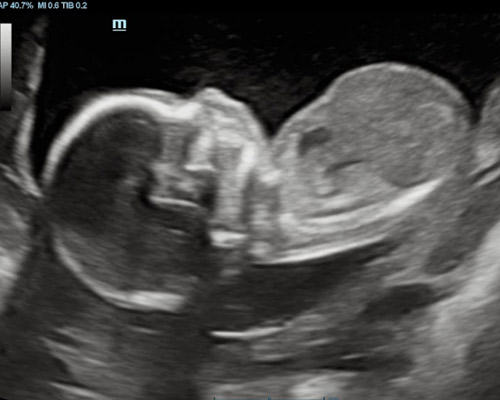

A reassurance scan is an ultrasound carried out during pregnancy to check how your baby is doing and to offer extra peace of mind between routine appointments. Many parents choose this type of scan when they want a closer look at their baby’s progress or simply wish to see them again.

During the scan, the sonographer looks at key signs of development such as heartbeat, movement, overall activity and positioning within the womb. This non-invasive method provides a clear picture of how things are progressing and can help ease common worries.

For many families, a reassurance scan near Worksop becomes a reassuring and memorable experience, especially when they can watch their baby moving on the screen.

- Observe your baby’s movements during the scan

- Visual confirmation of the fetal heartbeat

You may be able to see your baby’s movements, heartbeat, position and general activity during the scan.